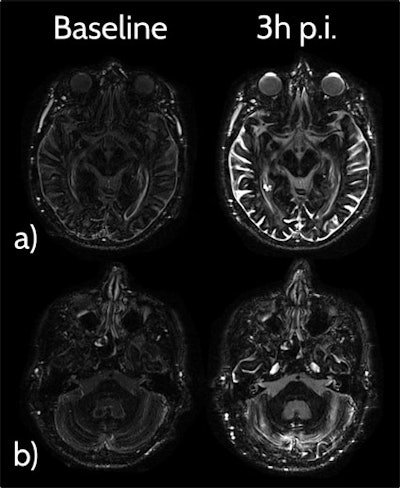

Heavily T2-weighted fluid-attenuated inversion-recovery (FLAIR) MR images were obtained before and three hours and 24 hours after intravenous GBCA application in 33 neurologically healthy patients and seven patients with an impaired blood-brain barrier due to cerebral metastases. The Heidelberg team determined signal intensity in various cerebral fluid spaces and quantified white-matter hyperintensities by applying the Fazekas scoring system.

They used delayed heavily T2-weighted FLAIR to show GBCA entry into the central nervous system (CNS) via the choroid plexus and the ciliary body, with GBCA drainage along perineural sheaths of cranial nerves and along perivascular spaces of penetrating cortical arteries. In all patients and all sites, they found a significant signal intensity increase for the three hours and 24 hours time points compared with baseline.